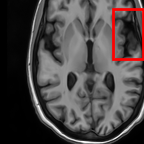

Sparsity Ikzsubscriptsuperscript𝐼𝑧absent𝑘I^{z}_{\downarrow k} LI 2D CNN 3D CNN Ours GT Ikz+1subscriptsuperscript𝐼𝑧1absent𝑘I^{z+1}_{\downarrow k}

4 Refer to caption Refer to caption Refer to caption Refer to caption Refer to caption Refer to caption Refer to caption

Refer to caption Refer to caption (a) 27.37/0.8465 Refer to caption (b) 32.34/0.9441 Refer to caption (c) 32.72/0.9436 Refer to caption (d) 34.11/0.9607 Refer to caption (e) PSNR(dB)/SSIM Refer to caption

8 Refer to caption Refer to caption Refer to caption Refer to caption Refer to caption Refer to caption Refer to caption

Refer to caption Refer to caption (f) 25.51/0.7681 Refer to caption (g) 28.29/0.8205 Refer to caption (h) 29.51/0.8824 Refer to caption (i) 31.87/0.9249 Refer to caption (j) PSNR(dB)/SSIM Refer to caption

Figure 5: Visual comparisons of slice interpolation approaches. For 4x sparsity, the second of three interpolated MR slices is presented. For 8x sparsity, the third of seven interpolated slices is presented.

5.3 Visual Comparisons

In Fig. 5, we present the observed slices Ikzsuperscriptsubscript𝐼absent𝑘𝑧I_{\downarrow k}^{z} and Ikz+1superscriptsubscript𝐼absent𝑘𝑧1I_{\downarrow k}^{z+1} along with the interpolated slices produced by different methods. Specifically we demonstrate the second of three interpolated MR slices for 4x sparsity, and the third of seven interpolated slices for 8x sparsity. We highlight the region where the anatomical structures significantly change compared to the observed slices Ikzsubscriptsuperscript𝐼𝑧absent𝑘I^{z}_{\downarrow k} and Ikz+1subscriptsuperscript𝐼𝑧1absent𝑘I^{z+1}_{\downarrow k}. We observe that although 2D CNN has comparable performance in terms of PSNR and SSIM, it tends to produce false anatomical structures in the zoomed regions. 3D CNN is able to resolve more accurate details. However, the improvement is quite limited, which we attribute to the fact that 3D CNN requires more training MR volumes in order to generalize and has smaller receptive field due to patch-based training. Our method benefits from the large receptive field of 2D CNN and two-view fusion, which not only produces sharper images, but also correctly estimates brain anatomy. The sharp and accurate estimation is crucial in clinical applications such as diagnosing Alzheimer’s Disease by brain volume estimation.